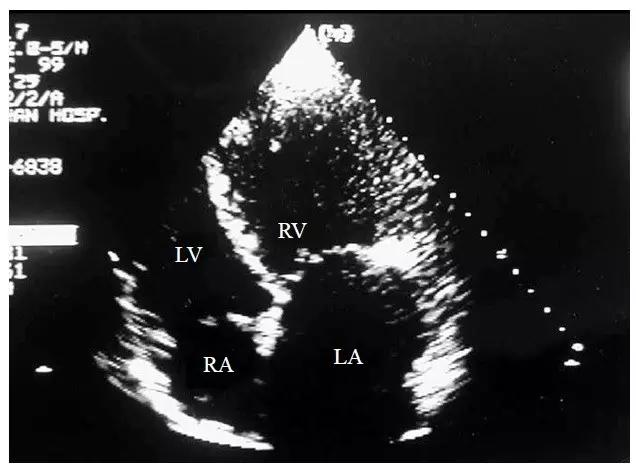

为了确定大动脉与心室的连接关系,首先应分辨左右心室。左心室和右心室主要根据房室瓣和肌小梁的特征来确定,即含三尖瓣的心室为右心室,含二尖瓣的心室为左心室(图10-4-7)。右心室的内膜面肌小梁较丰富,含有调节束,而左心室的内膜面较光滑,带有假腱索。一旦确定了心室的属性,再要确定大动脉与心室的连接关系就不难了。通常我们先取心尖四腔心切面,然后探头逐步向上跷起显示心尖五腔心切面,同时观察主动脉和肺动脉与心室的连接关系。由于肺动脉在后,主动脉在前,所以在探头上跷的过程中总是先出现肺动脉,然后才出现主动脉。如果两根大动脉与心室的连接不一致,即肺动脉与左心室相连,主动脉与右心室相连,即为大动脉转位,反之则为大动脉异位。

图10-4-7 大动脉转位心室左襻的二维超声心动图表现

心尖四腔心切面示右心室位于左侧,左心室位于右侧,三尖瓣隔叶的位置较二尖瓣低,右心室内可见调节束(LA-左心房 LV-左心室 RA-右心房 RV-右心室)